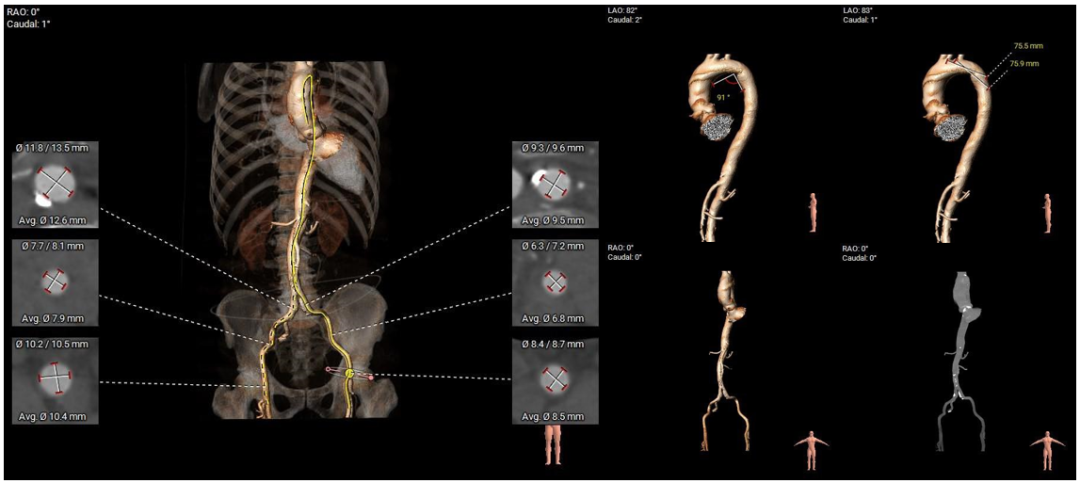

• 腹主动脉、双侧髂总动脉可见多发散在钙化斑块,双侧股髂动脉未见明显扭曲、狭窄,左侧股动脉分叉点偏高,入路血管内径尚可。

外周血管入路评估

• 腹主动脉、双侧髂总动脉可见多发散在钙化斑块,入路血管内径尚可,术中注意规范操作。